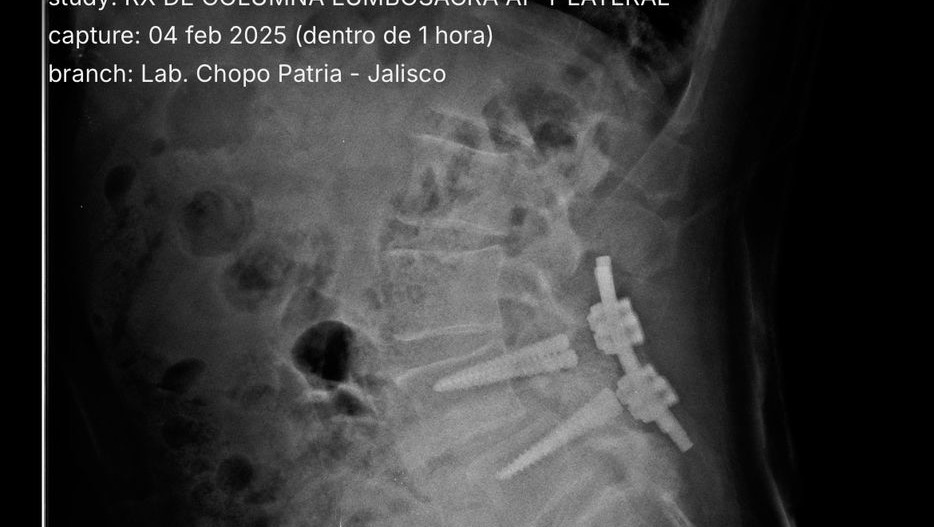

Es extremadamente raro que los tornillos se rompan todos. Se puede romper uno, o dos, pero cuatro es un caso especial y preocupante.

Él fue operado por la Seguridad Social en Agosto de 2019, pero sufrió una caída catastrófica en Mayo de 2021, donde el implante que le fue puesto, sufrió la rotura de todos los tornillos de titanio que le habían colocado (cuatro), con lo que la placa que los unía, quedó flotando. Esto le ha provocado mucho dolor y complicaciones, llegando incluso a no poder caminar, y esto se ha agravado en los últimos días.

Es necesario, por supuesto, colocar nuevos tornillos, en esta ocasión 8 de ellos, más otros elementos necesarios, como placa y un puente que los una. Además, nos indico la necesidad de donaciones de sangre +B, de la que nos haremos cargo nosotros, que tenemos la misma sangre que nuestro Papá.